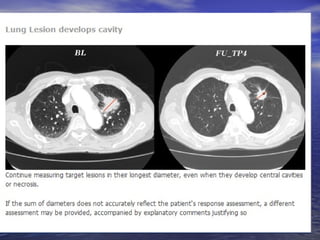

Lesões pulmonares escavadas:

Controverso o método de mensuração.